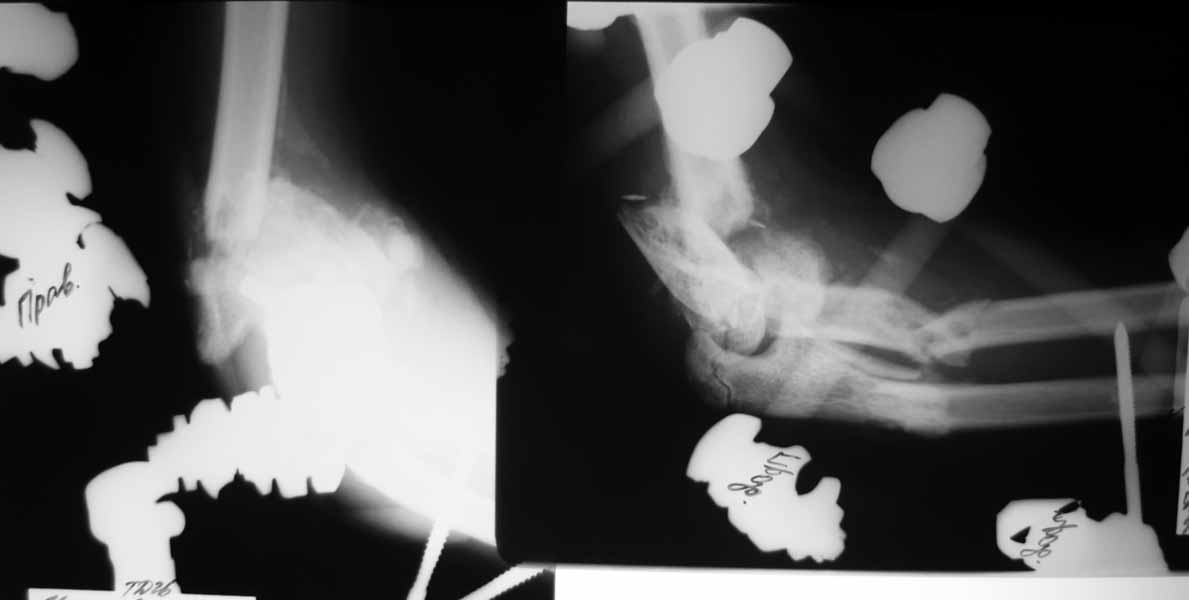

Насколько оправдано снятие аппарата? В АВФ удобнее мыть, перевязывать, не так ли? Штанги графитовые и больших наводок при рКТГ не дадут. Выкладываю свежие рентгенограммы.

Согласен, при таком "качестве" снимков КТ необходимо. По поводу дистального метафиза - при благоприятном сопоставлении суставных опорных поверхностей - дефект заполнить не составит большого труда.

Мысли такие: на завтра сделаем некрэктомию участков локального сухого некроза кожи на локтевом суставе. Заживляем-первязываем. Лучевую кость есть желание синтезировать закрыто ESIN под ЭОП. Локтевую кость - открыто, как в пункте 4. Скорее всего - БИОС. Пункт 4 не вызывает никаких возражений. Смущает фраза первого оперирующего: что все отломки "вбиты в мышцы как при разделке мясником и обмотаны фасциями". При таком взаимоотношении с мягкими тканями сложно расчитывать на изящный выход из ситуации.